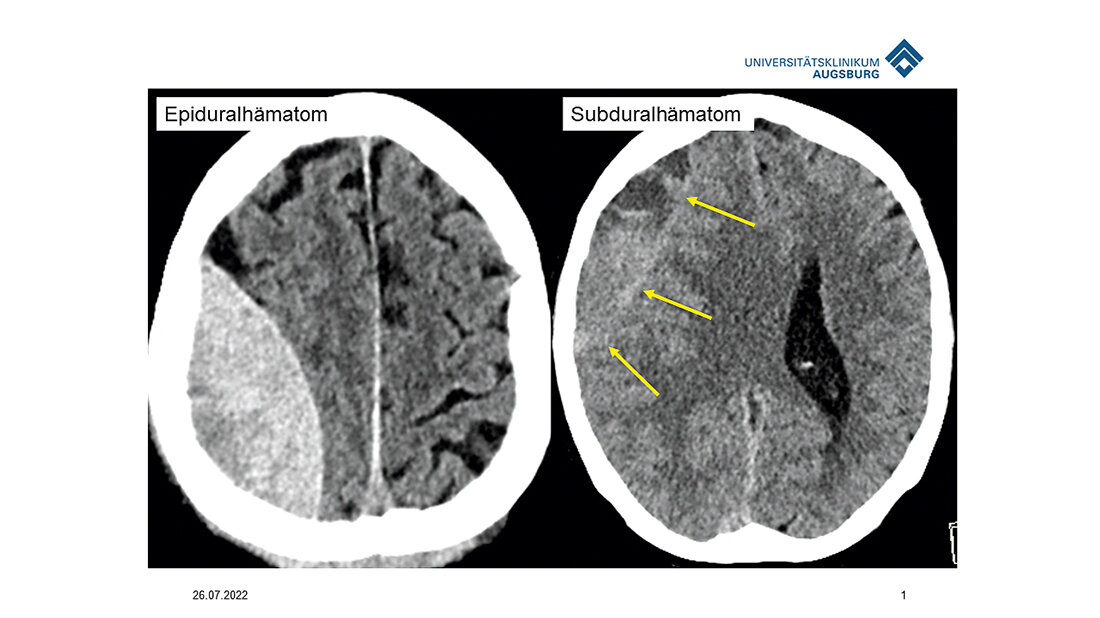

Eine weitere Ursache bei Älteren ist eine gewisse Schrumpfung des Gehirns; wenn sich dieses im Hirnwasser bewegt, kann es zu Abrissen von Venen und somit Blutungen kommen. Diese sind lebensbedrohlich; sie müssen innerhalb kürzester Zeit versorgt werden. Die maximale Zeit bis zum Eingriff betrage vier bis fünf Stunden, fährt der Radiologe fort.

Chronisch subdurale Hämatome betreffen vornehmlich ältere Menschen mit altersbedingter Volumenminderung; von diesen Hämatomen werden immer mehr verschlossen, seit die Pathologie besser verstanden wird. Wenn sich die Therapie durchsetze, betont der Radiologe, werde dies ein umfangreiches Patientengut betreffen.